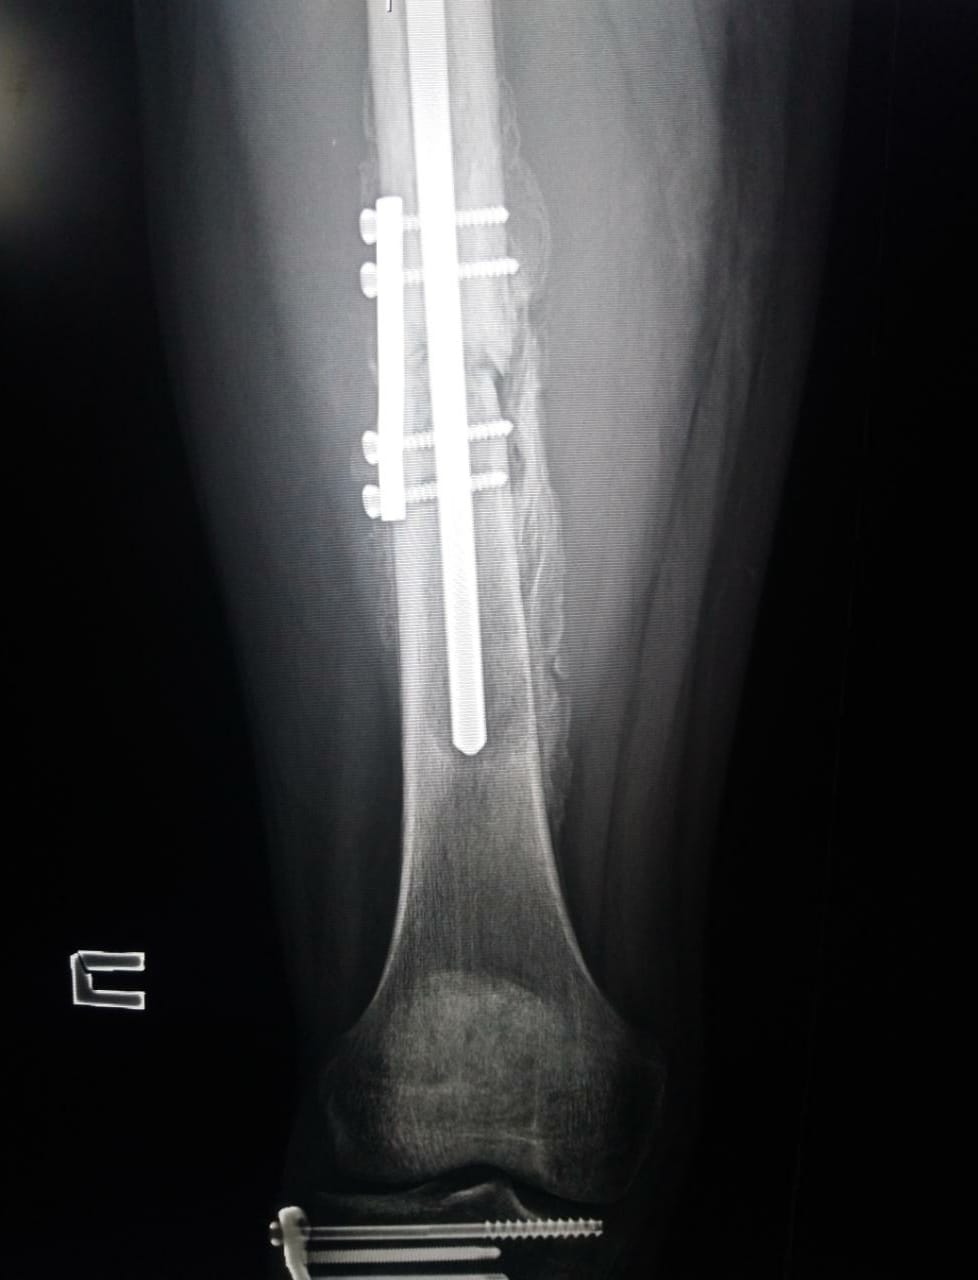

Пример типичного перелома диафиза бедренной кости и операционная фиксация

Как отметил Пирро, авария произошла утром, практически сразу после открытия пит-лейна. Как подтвердили инсайдеры, Фермин Альдегер катался на арендованном Yamaha R6, а не на тренировочном Ducati. На холодном асфальте он поймал хайсайд, вылетел в гравий, откуда его забрала скорая помощь. Первый же медосмотр дал четкое представление о травме - перелом бедра. Более детальный осмотр дал диагноз: перелом диафиза (тела) левой бедренной кости.

Гонщик Gresini Racing был эвакуирован в Барселону, где вчера ему должны были провести срочную операцию по фиксации кости. Команда сегодня официально подтвердила всё это и объявила, что операция прошла успешно.